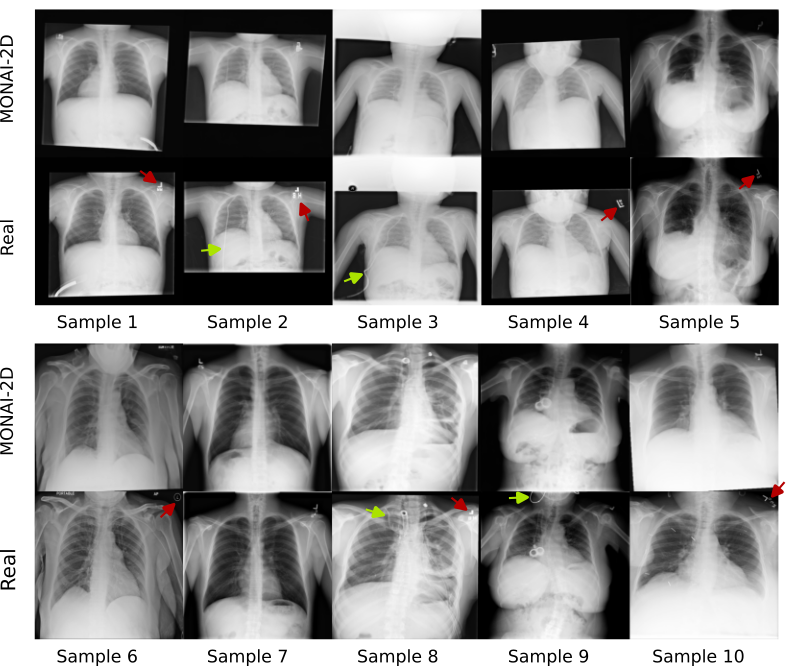

Refer to caption

Figure 7: Representative cross sections of real (Real) and copies (MONAI-2D) detected in the X-ray dataset. Copy candidates show a high resemblance to the corresponding real samples. The network tends to copy even the exact position of the image in case of partial field-of-view coverage.

In the 2D X-ray dataset, 32.6 % of the training data were memorized and 54.5% of the synthetic samples were patient data copies in MONAI-2D. Fig. 7 shows copies alongside the closest training samples. Synthetic samples show a very close resemblance to the training samples. Overall, we observed a high level of patient data was memorized in both 2D and 3D models. Moreover, a very large percentage of synthesized samples were patient data copies, especially in 3D models.